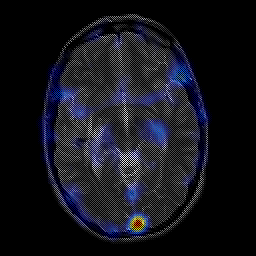

overlay -- Slice #12

[Home][Help][Clinical] Slice 12